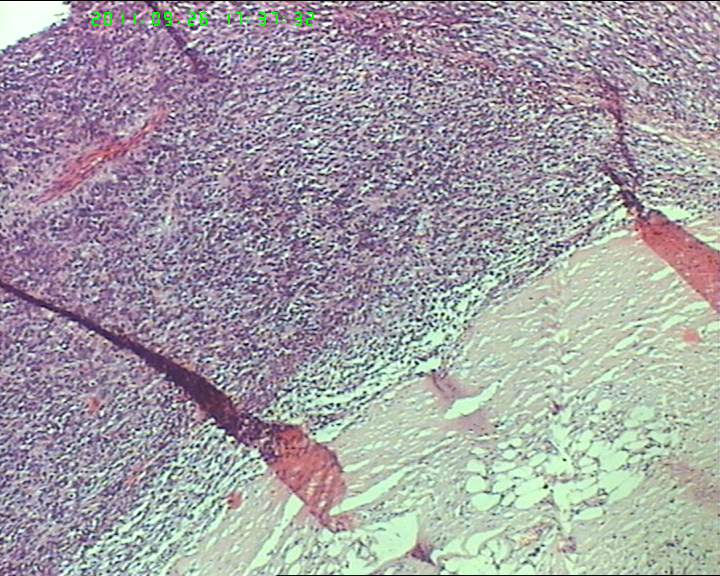

包块与大网膜粘连,根部附着于肠系膜,脾曲处有较多积血块 但无活动性出血,肠系膜上有较多粟粒样结节,白色质韧。与子宫 输卵管 卵巢没有关系.

灰白不整形肿物一个,大小18*15*9cm,表面结节状,包膜完整,切面灰白,中央可见坏死区,质软,范围5*4cm。其余切面多彩 部分半透明状 质中。

鉴别诊断排排队:1、GIST,2、MPNST,3、去分化脂肪肉瘤,4、恶性间皮瘤,5、恶性SFT,6、平肉